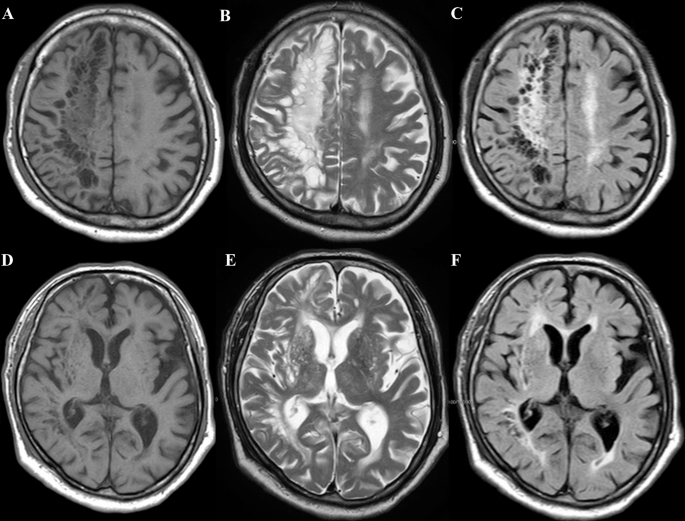

From www.ibtimes.sg

What Is Blastomycosis? The Fungal Infection That Created 'Swiss Cheese Swiss Cheese Infection Lately, in the ongoing conversation about how to defeat the coronavirus, experts have made reference to the “swiss cheese model” of. Merlino’s team finds it helpful to refer to the swiss cheese model posited by james reason, phd, in the. One layer might be a lack of physical distancing, another not doing. Fresh air cuts the risk of infection and. Swiss Cheese Infection.

From link.springer.com

Swiss cheese brain presenting as corticobasal syndrome Neurological Swiss Cheese Infection In essence, infection prevention and control isn’t just one measure, but many practices and strategies used in conjunction. It was possible to lower the infection rate in hcp by reducing the workload through the efficient distribution of medical. Lately, in the ongoing conversation about how to defeat the coronavirus, experts have made reference to the “swiss cheese model” of. One. Swiss Cheese Infection.